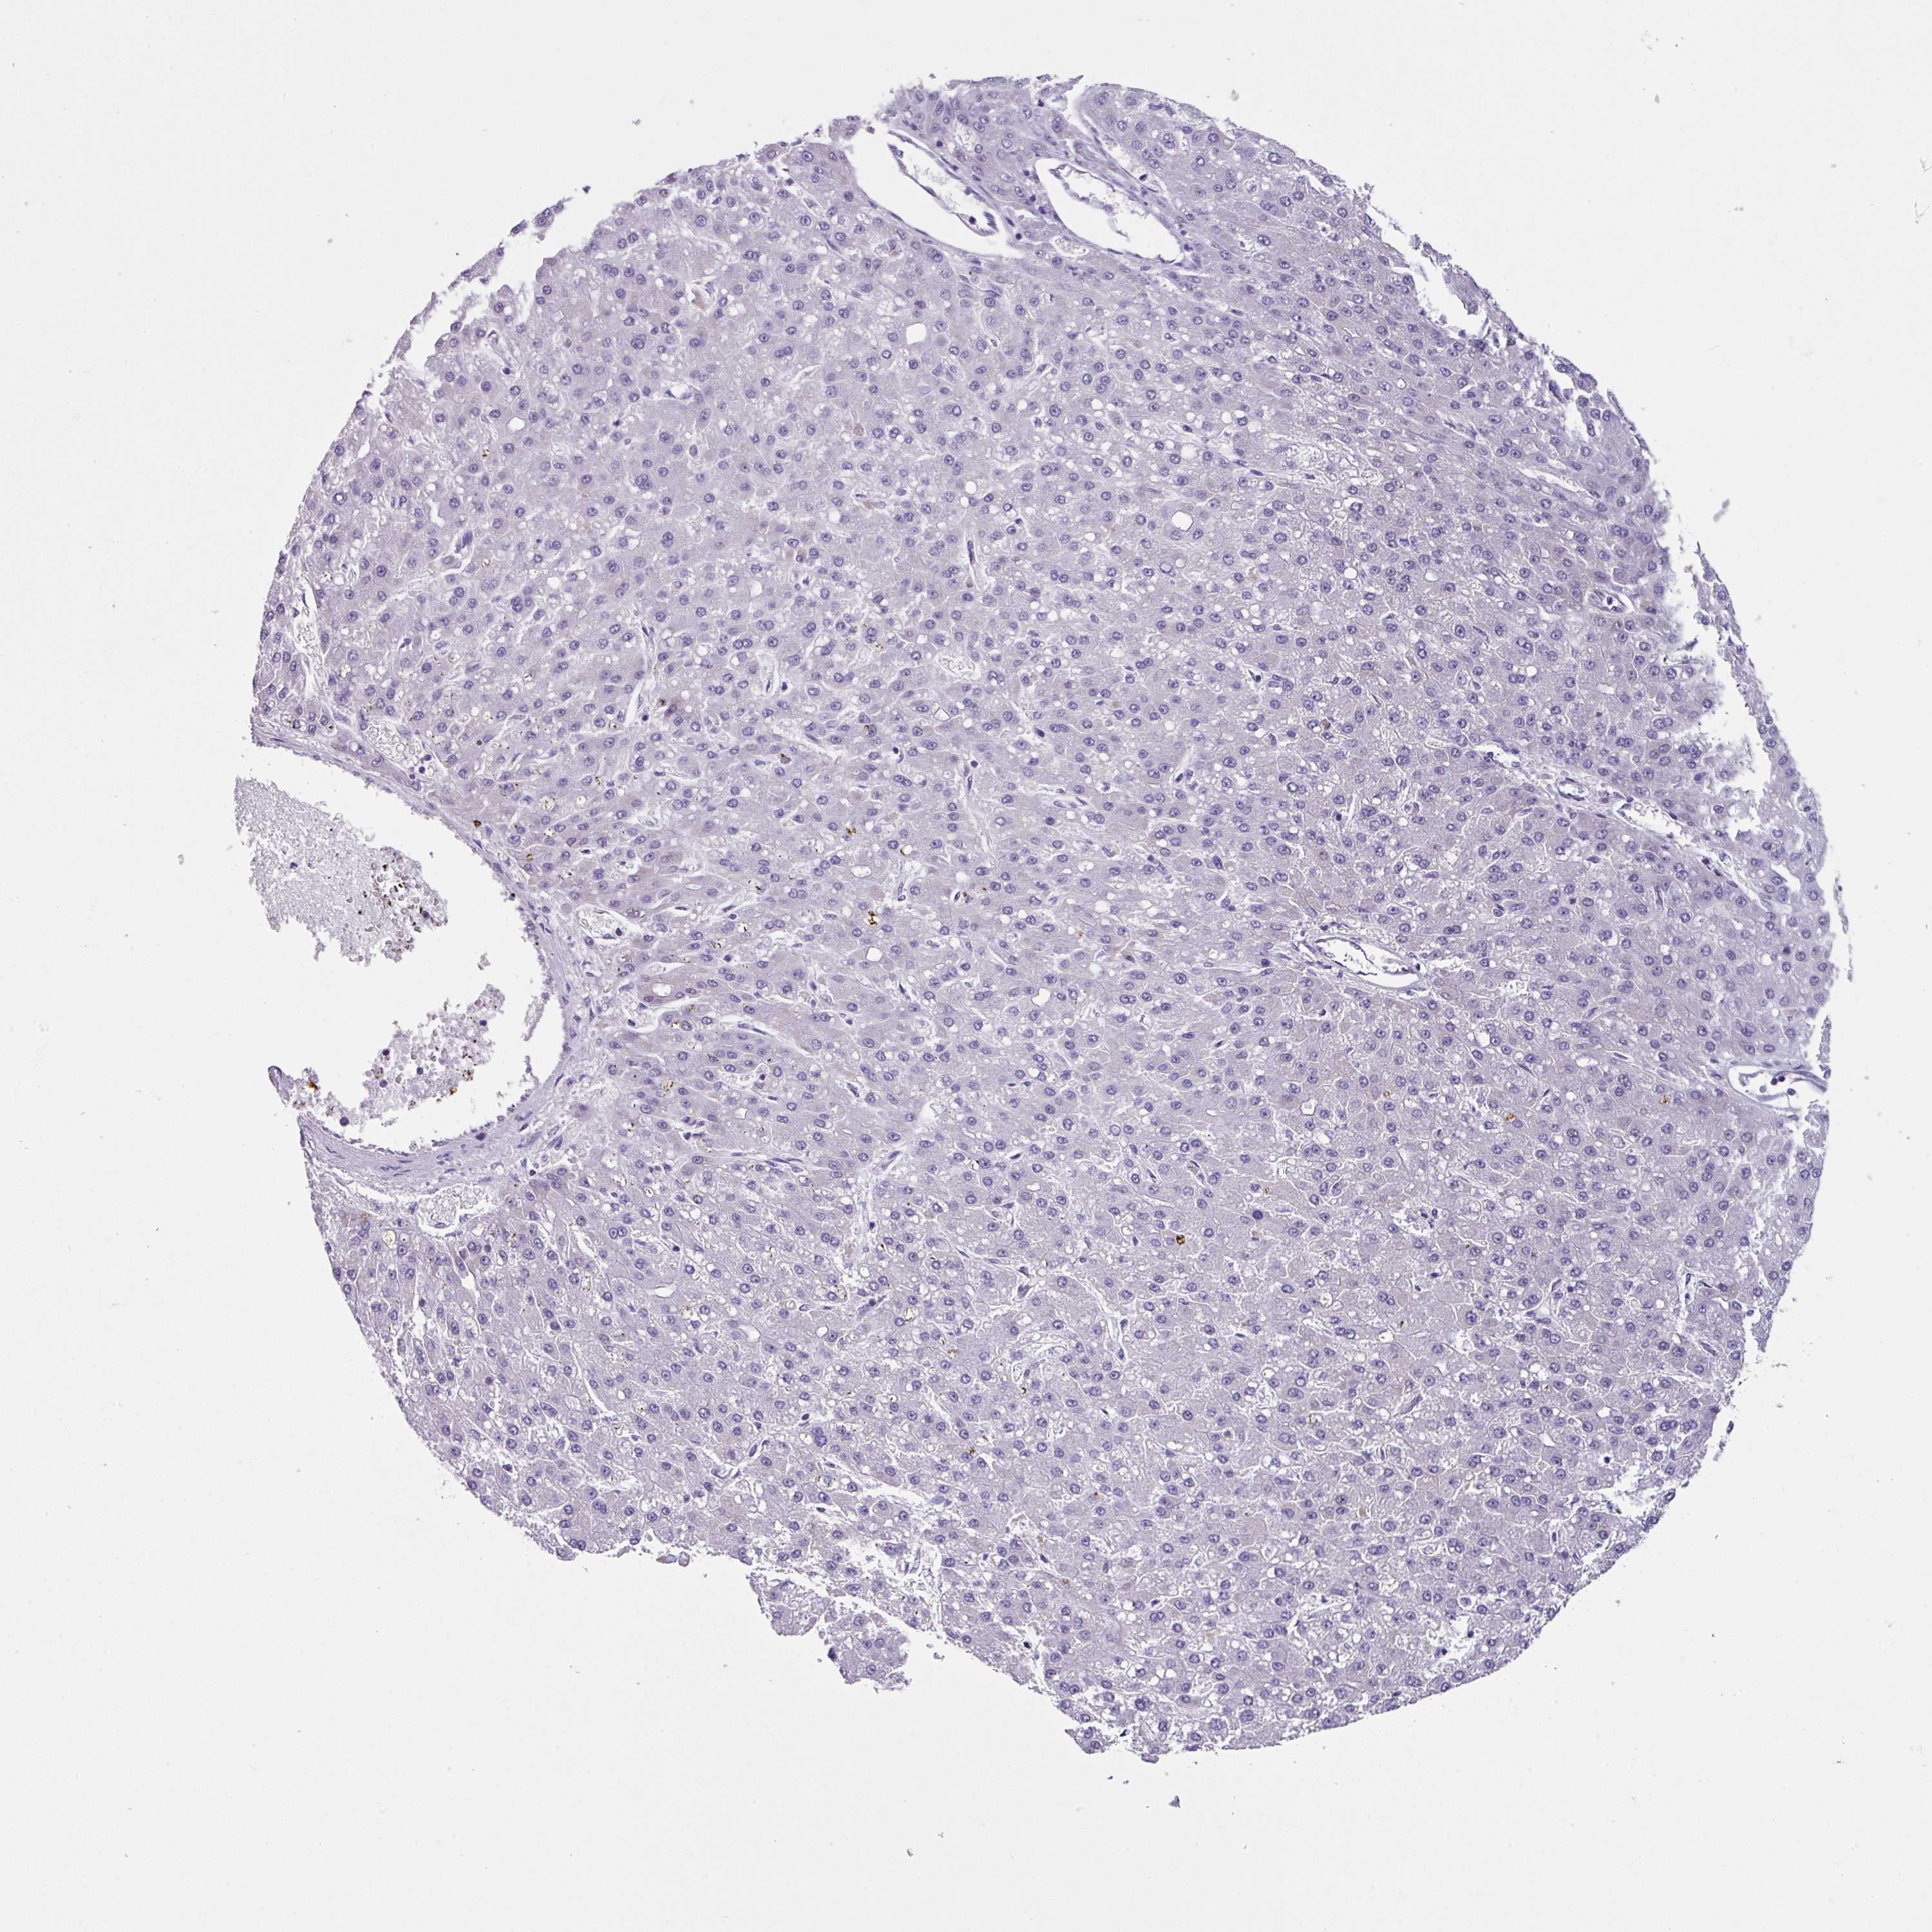

LIVER CANCER - Protein expressioni

A mouse-over function shows sample information and annotation data. Click on an image to view it in a full screen mode. Samples can be filtered based on level of antibody staining by selecting one or several of the following categories: high, medium, low and not detected. The assay and annotation is described here.

Note that samples used for immunohistochemistry by the Human Protein Atlas do not correspond to samples in the TCGA dataset.

Antibody stainingi

Antibody staining in the annotated cell types in the current human tissue is reported as not detected, low, medium, or high, based on conventional immunohistochemistry profiling in selected tissues. This score is based on the combination of the staining intensity and fraction of stained cells.

Each image is clickable and will lead to virtual microscopy that enables deeper exploration of all samples and also displays staining intensity scores, fraction scores and subcellular localization as well as patient and tissue information for each sample.

Antibody HPA053085

Staining

High

Medium

Low

Not detected

Intensity

Strong

Moderate

Weak

Negative

Quantity

>75%

75%-25%

<25%

None

Location

Nuclear

Cytoplasmic/membranous

Cytoplasmic/membranous,nuclear

Cholangiocarcinoma

Carcinoma, Hepatocellular, NOS